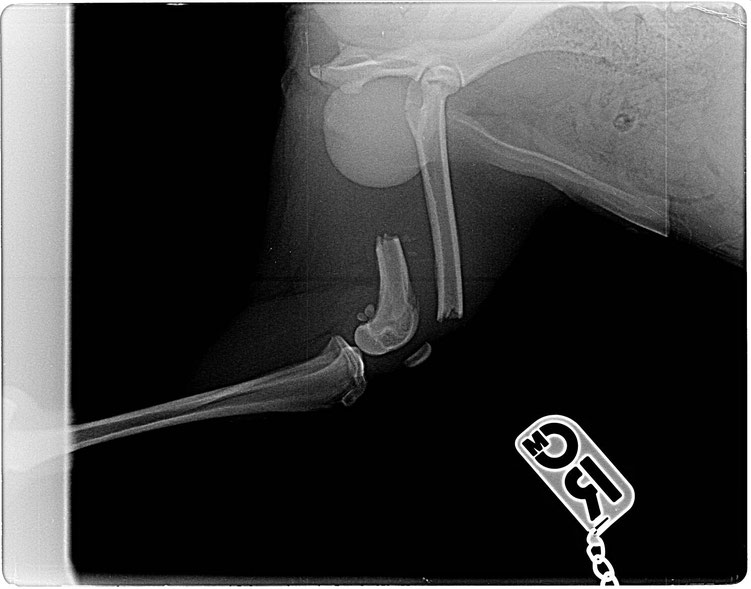

Kirby wurde nun erneut geröntgt und es stellte sich heraus, dass die Aufnahmen beim ersten Röntgen leider aus einem falschen Winkel gemacht worden waren, so dass der Bruch des Ellenbogens nicht

gesehen werden konnte.

Vermutlich handelt es sich sogar um eine Trümmerfraktur, was einen komplizierten Eingriff zu Folge haben wird. Außerdem hat sich eine Entzündung im Gelenk eingenistet, so dass leider auch noch nicht sicher ist, ob Kirby sein Bein wird behalten können.

Wie befürchtet, hat sich der Verdacht leider bestätigt: Kirby hat eine Trümmerfraktur des Ellenbogens.